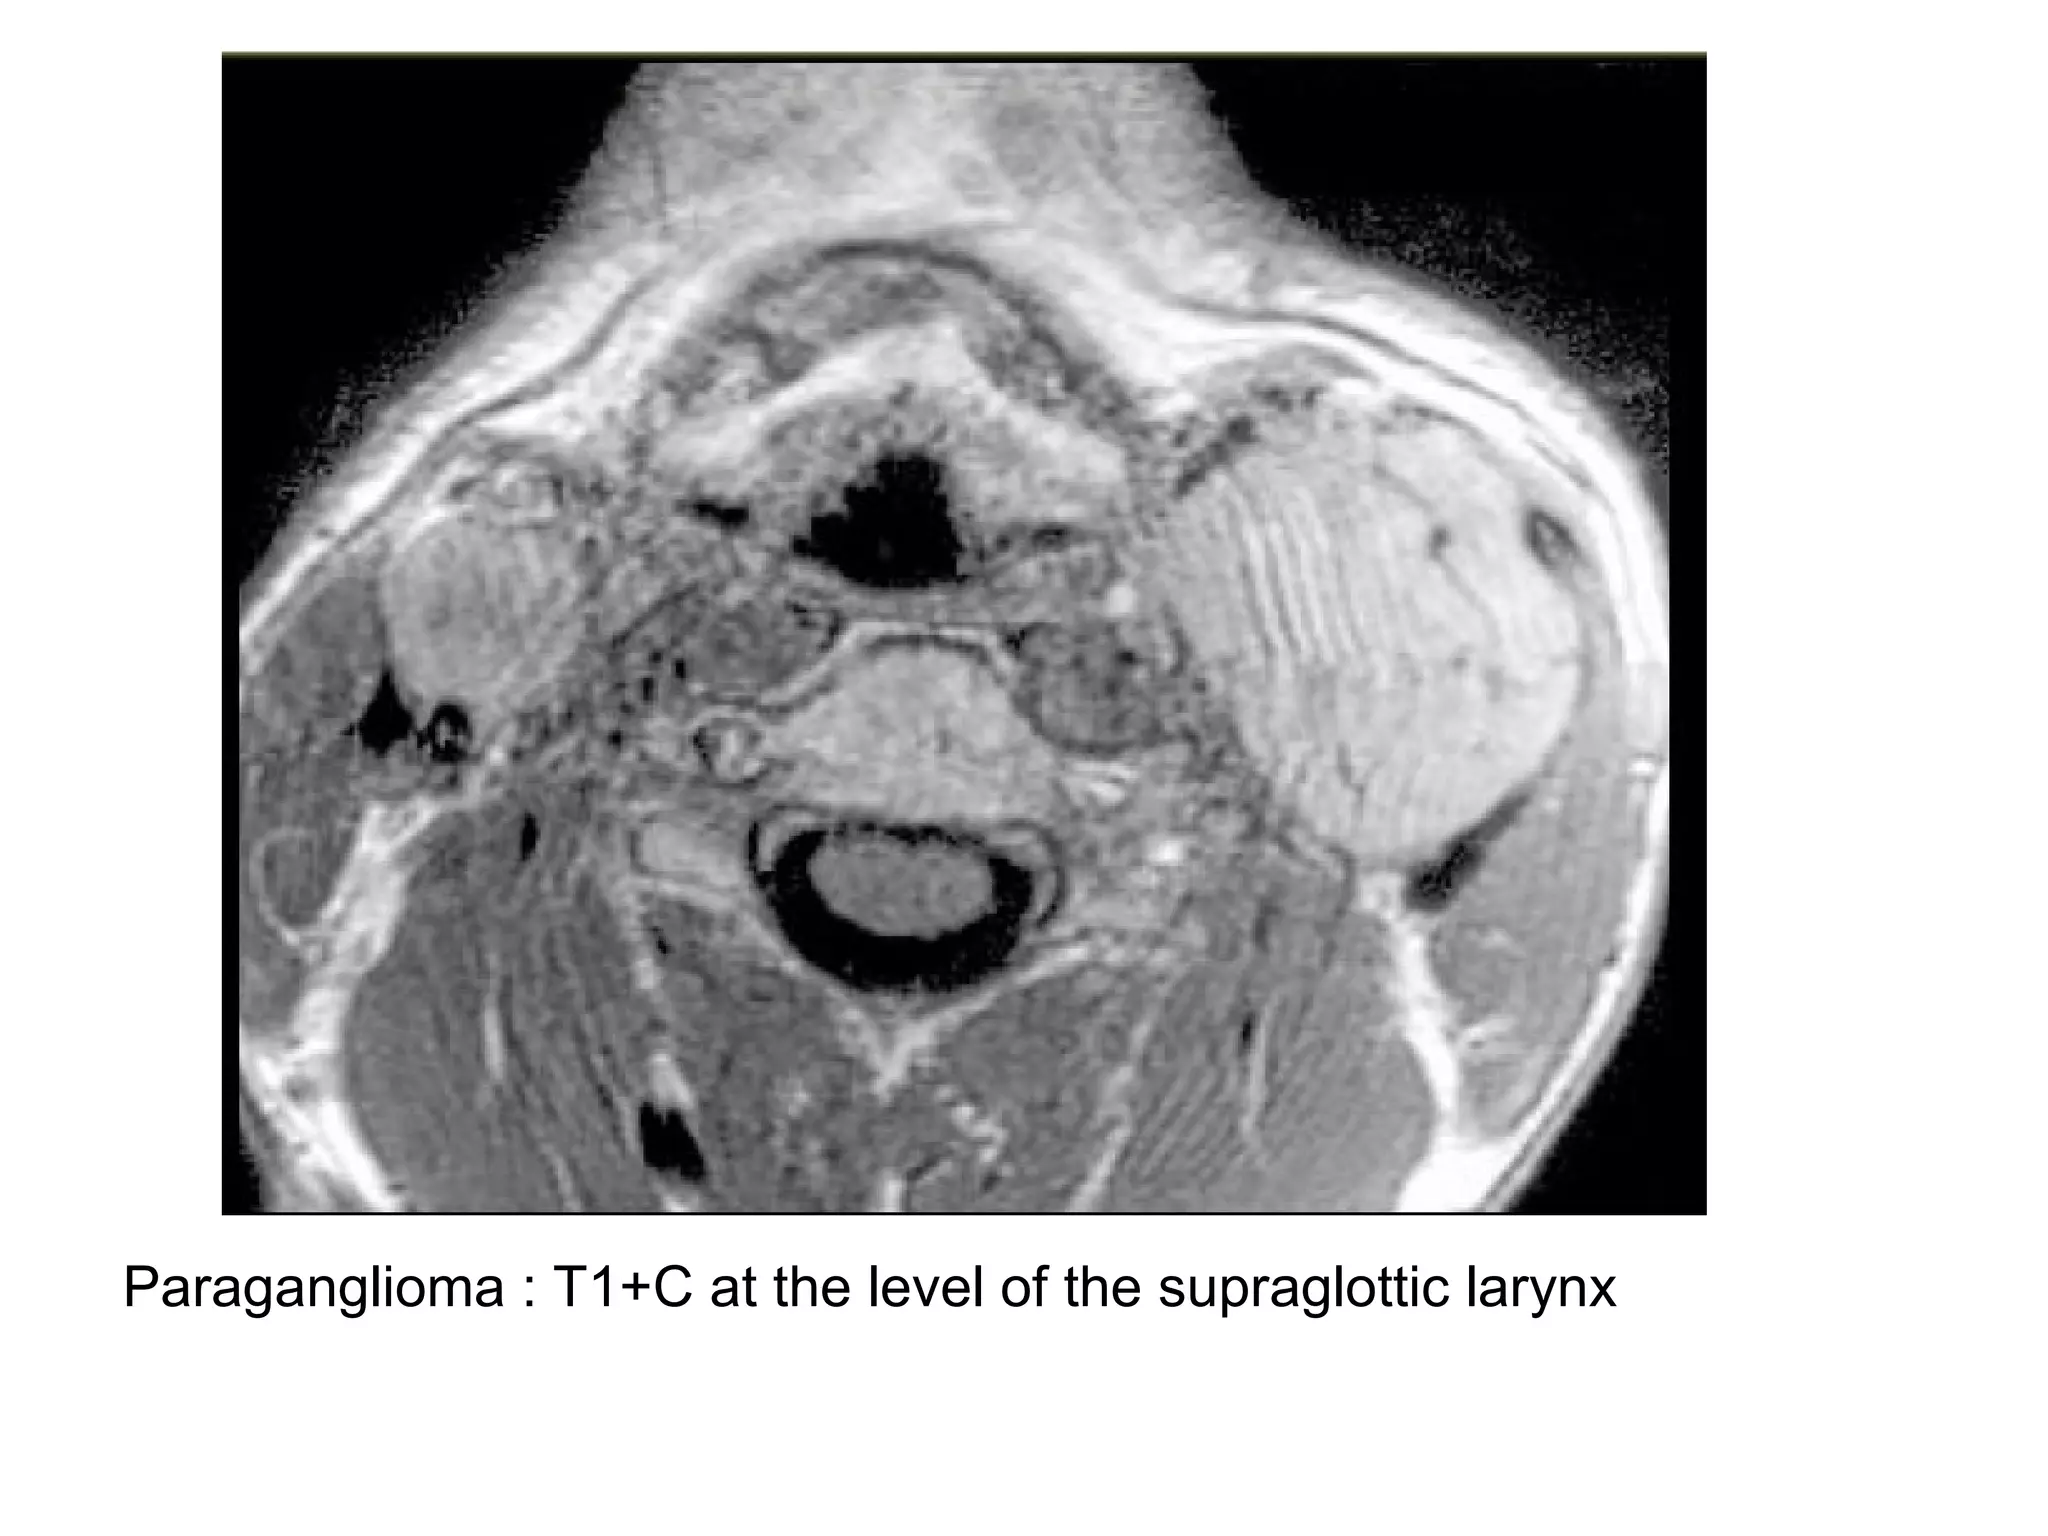

Paraganglioma : T1+C at the level of the supraglottic larynx

Paraganglioma : T1+Cat the level of the supraglottic larynx